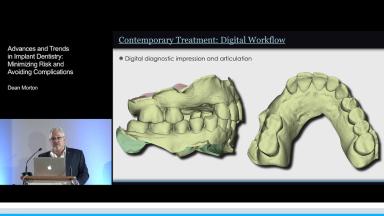

This lecture explains the trends in implant dentistry in a digital world: using digital impressions to obtain milled, printed, or digital casts; designing virtual prostheses via digital diagnostic wax-ups; and incorporating the patient’s cone beam CT into a digital workflow. This practice philosophy embraces prosthodontic-driven treatment planning in completely and partially edentulous arches through identifying the ideal prosthesis and creating prefabricated components. This presentation further demonstrates how this philosophy can lead to uneventful treatment that minimizes complications. The speaker emphasizes the key relationships between teeth, lips, and the residual ridge that indicate the optimal three-dimensional position for implant prostheses, and he advocates for the use of interim prostheses.

- describe the digital workflow for implant therapy